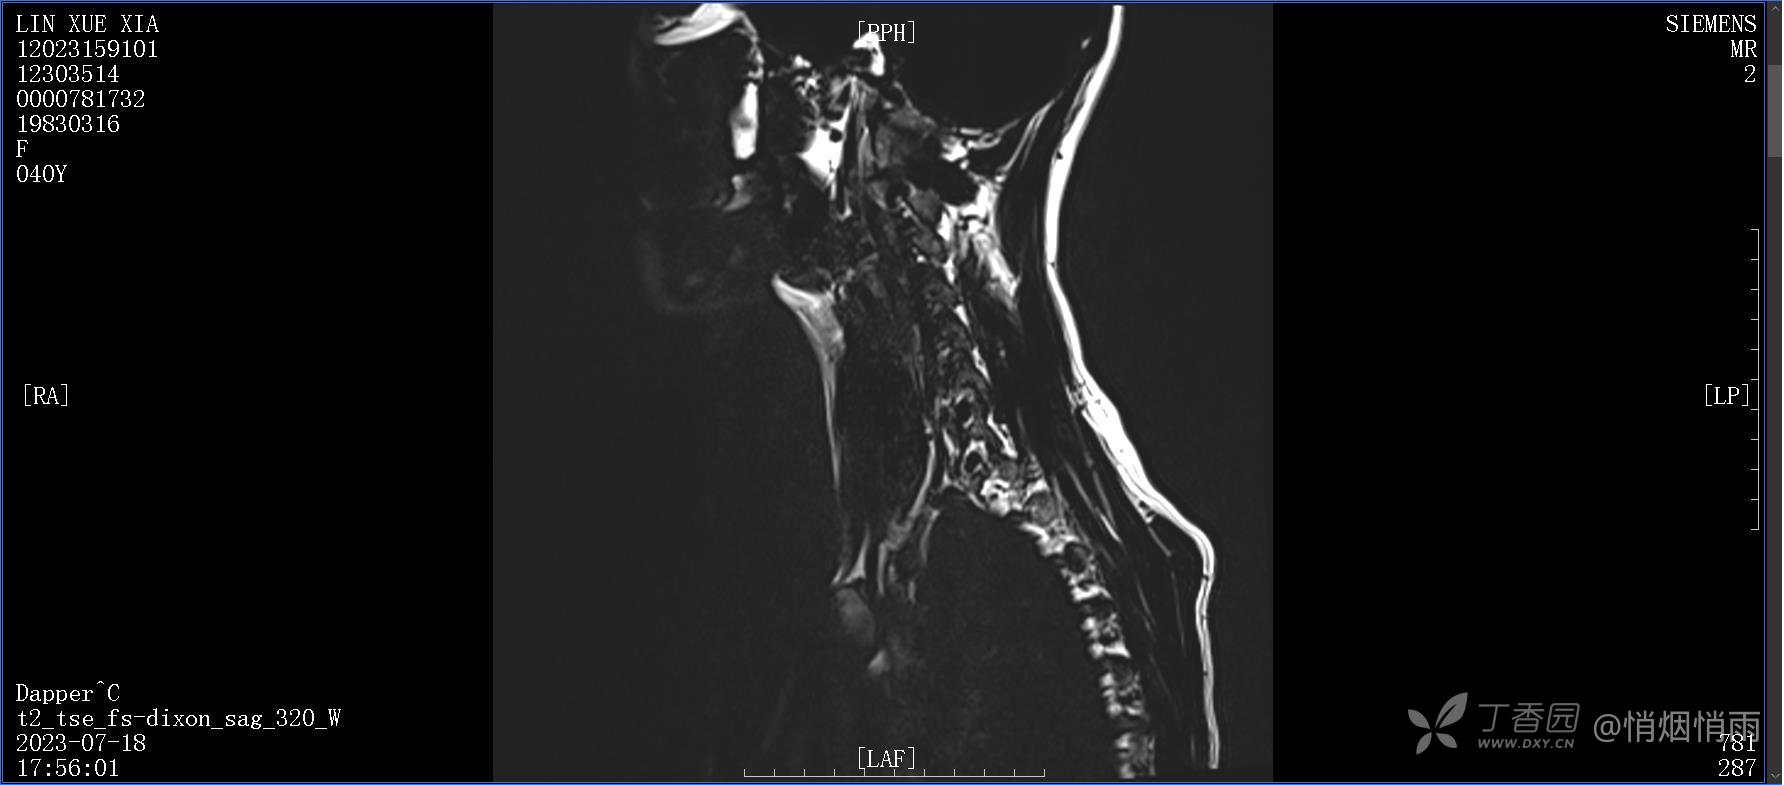

不明原因的右肩背部疼痛

NeurothinkerZ 推荐患者女性,40岁,因右肩背部疼痛班活动受限4日余入院(2023-07-17)。

病史:入院前4天无明显诱因突然感右肩背疼痛伴随活动受限,自行口服依托考昔、艾瑞昔布等药物治疗,院外应用肩关节局部手法按摩等,均无明显改善。外院门诊诊为颈椎病。自诉既往多次“胸椎小关节紊乱”于当地诊所行手法按摩,治疗后好转,否认慢性疾病病史、外伤史、手术史,诉青霉素过敏,无其他药物食物过敏史,否认吸烟史、饮酒史,月经正常,经量正常。

目前的诊断,暂时依据辅助检查诊为肩袖损伤,但是患者疼痛的性质和特点,却不是单纯的肩袖损伤所致。考虑过胸廓出口综合征,但是该疾病会出现肩胛区的疼痛吗?(由于考虑到费用的问题,没再进行下一步的检查)带状疱疹会有如此的症状吗?